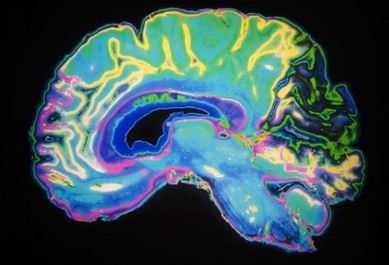

Tests of brainwaves using EEG may be helpful in distinguishing subtypes of ADHD, helping to diagnose whether a teen’s symptoms are mainly inattention or mainly hyperactivity and impulsiveness.

The two subtypes of attention-deficit/hyperactivity disorder (ADHD) are known as “inattentive” or “combined” and as well as telling these apart, the brain tests also help to rule out normal adolescents.

The researchers, publishing their study in the journal Biological Psychiatry, say the electroencephalogram (EEG) readings illustrate “that these groups display distinct physiological profiles.”

This means there may be an objective biological test for differences that are subjectively observed in the clinic.

“This study shows that there are changes in brainwaves related to visual processing and motor planning that can be used to distinguish ADHD subtypes,” says Ali Mazaheri, assistant professor University of Amsterdam, the Netherlands, and guest researcher at the Center for Mind and Brain of the University of California, Davis.